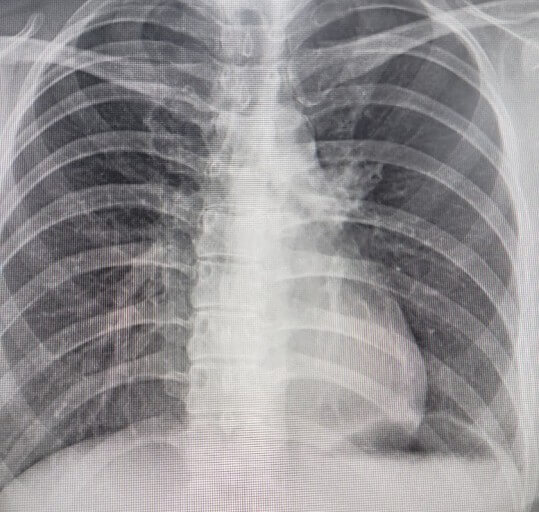

폐렴 초기증상

1) 기침과 가래

폐렴 초기증상의 대표적인 문제는 역시 기침과 가래입니다. 일상 속에서 꾸준한 기침과 가래를 유발할 수 있고 가래는 더욱 끈적하고 고름처럼 나오기도 합니다.

2) 발열

성인 폐렴 증상의 경우 발열이 발생할 수 있는데요. 기침과 함께 발생하게 되며 38도 이상의 고열을 유발하는 경우가 많습니다. 이 때문에 감기로 오인하기도 합니다.

3) 가슴통증

폐렴초기증상의 경우 가슴통증과 같은 문제도 제공할 수 있습니다. 이는 호흡할 때 주로 흉통이 심해진다는 특징 때문이기도 한데요. 이는 폐를 둘러쌓고 있는 흉막에 염증이 생기기 때문에 발생하는 것입니다.